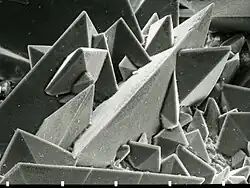

Ursachen

Die Entstehung von Nierensteinen ist von vielen Faktoren abhängig, die je nach Ausprägung zu verschieden zusammengesetzten Konkrementen führen. Viele Stoffwechselabläufe sind in diesem Zusammenhang noch ungeklärt. Auf molekularer Ebene kommt es zu einer Erhöhung der Konzentration von schwerlöslichen Ionenverbindungen oder anderen Harnbestandteilen bis zur Überschreitung des sogenannten Löslichkeitsprodukts. Dadurch beginnen diese Substanzen (Salze) auszufallen und Konglomerate zu bilden, die ab einer gewissen Größe die ableitenden Harnwege nicht mehr passieren können.

- Calciumoxalat-Steine (65 % Häufigkeit)